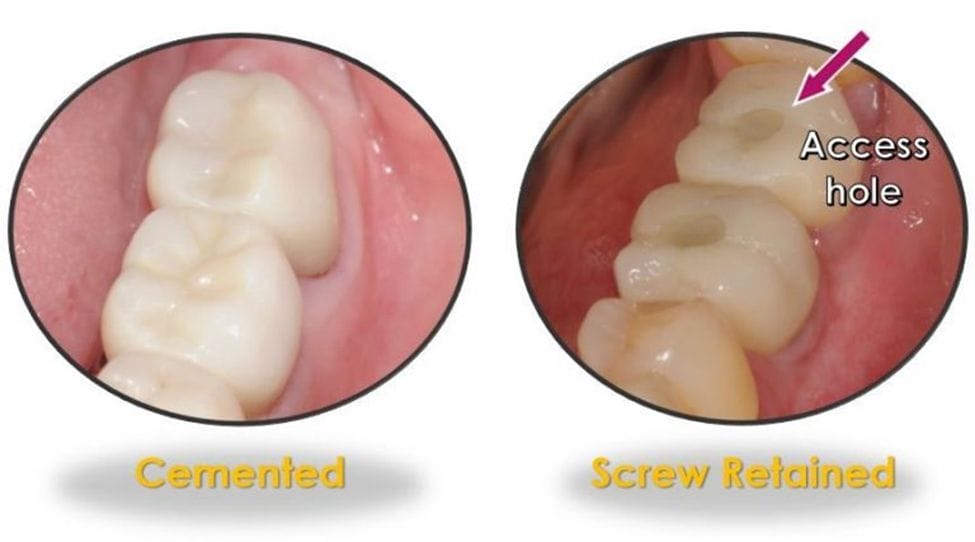

Not only that, but dental hygienists should also be knowledgeable about the different restorative types, their retention, and possible complications. For example, is the crown screw-retained, or is it cemented? Screw-retained implant restorations will have an access hole on the occlusal surfaces of posterior teeth and the lingual surfaces of anterior teeth and should be evaluated for any missing filling material (Figure 1). Cemented implant crowns need to be closely assessed for the possibility of residual cement, a well-documented risk factor for peri-implantitis 2-3, 9,12 (Figure 2).

Figure 1:

Figure 1: Images courtesy Shavonne Healy and Kazemi Oral Surgery and Dental Implants.Figure 2: